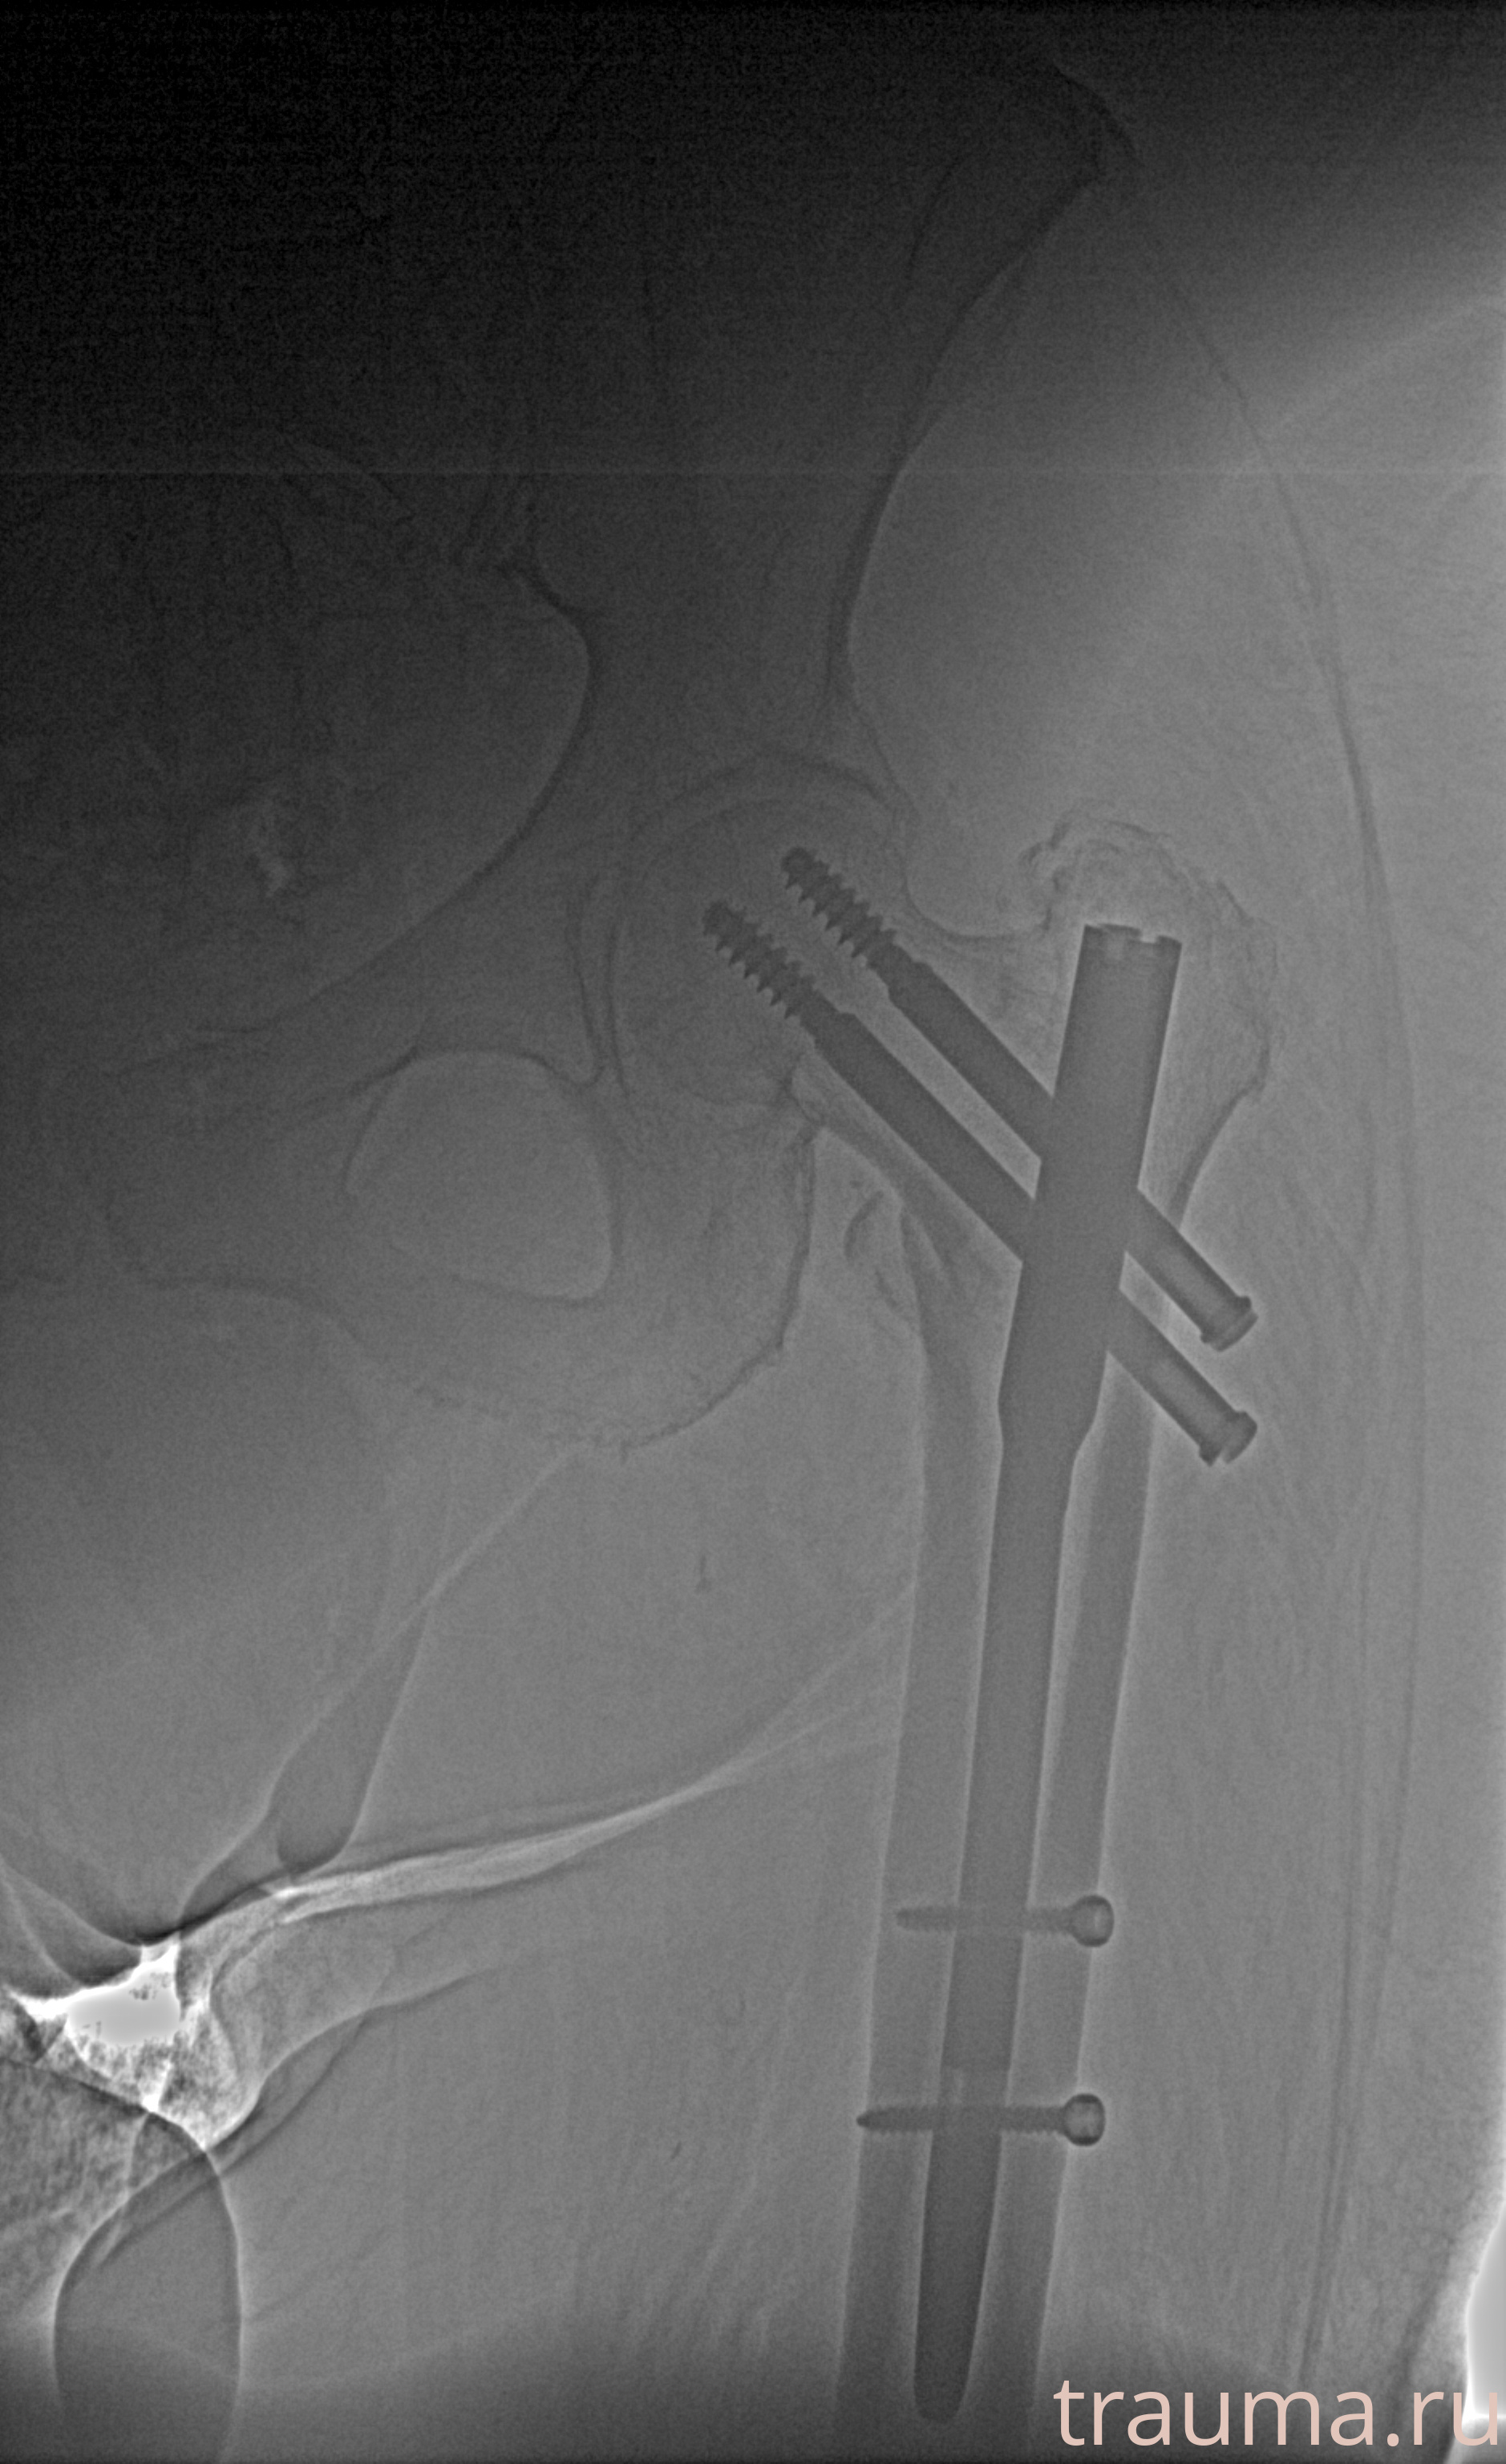

Рентгенограммы

Рентген на дому: по вашему адресу приезжает врач-рентгенолог, травматолог-ортопед с мобильным рентгеновским аппаратом, проводит диагностику травмы или заболевания, делает необходимые рентгенограммы, дает рекомендации по дальнейшему лечению. Получить качественные снимки в домашних условиях возможно благодаря уникальной методике, разработанной МосРентген Центром для института  Склифосовского